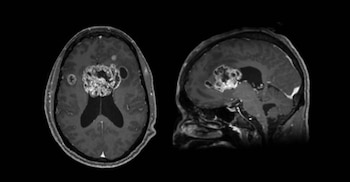

El ex jugador de la NBA Jason Collins se enfrenta uno de los desafíos más complejos de su vida tras ser diagnosticado con un agresivo cáncer cerebral, denominado glioblastoma, que se encuentra en una fase 4 de la enfermedad. En una entrevista, el retirado basquetbolista de 47 años reveló que el tumor es irresecable por los riesgos que implica una operación para extirparlo y que, pese a los tratamientos convencionales, el pronóstico promedio de supervivencia oscila entre 11 y 14 meses. Ante este escenario, optó por explorar terapias experimentales, con la esperanza de que puedan ofrecer una alternativa para su caso y, eventualmente, para otros pacientes.

Lo que siguió fue la consulta médica, en la que se descubrió el tumor cerebral mediante una tomografía computarizada y el diagnóstico de glioblastoma avanzado. Su esposo, Brunson Green, contó en el reportaje las palabras de los doctores: “Fuimos a urgencias y en cinco minutos nos dijeron que tenía un bulto del tamaño de una pelota de béisbol en medio del cráneo”.

El ex jugador describió a su enfermedad como “una mariposa que prácticamente lo invadió todo”, dando a entender la velocidad con la que se propagó el cáncer en su cuerpo. "Había terminado un tratamiento de radioterapia, pero el glioblastoma aprendió cómo volver a crecer. Había duplicado su tamaño en unas dos o tres semanas. Recuerdo que mi hermano me hablaba de la batalla a la que me iba a enfrentar. Me decía: ‘Tienes que luchar’. Y eso es lo que he hecho toda mi vida, luchar", prosiguió.